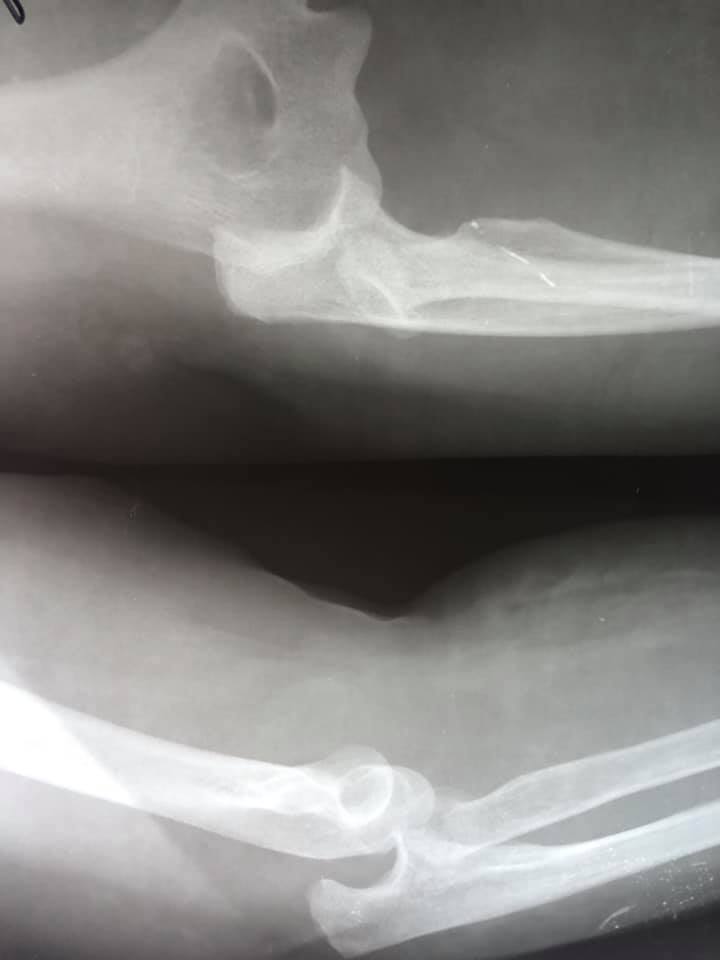

В ургентному порядку жінка звернулася в КНП «НЦМЛ». Після огляду був встановлений діагноз: травматичний вивих кісток правого передпліччя з повним відривним відламковим переломом голівки променевої кістки.

Проведена відкрита репозиція перелому та вивиху з внутрішньою фіксацією. В операційній працювали лікарі-ортопеди-травматологи: Родзь Тарас Яремович; Брус Роман Богданович. Анестезіологічне забезпечення Піддубний Юрій Федорович, лікар-анестезіолог; Бадзюнь Лілія Любомирівна, сестра медична-анестезистка. Магдюк Людмила Анатоліївна, сестра медична операційна.